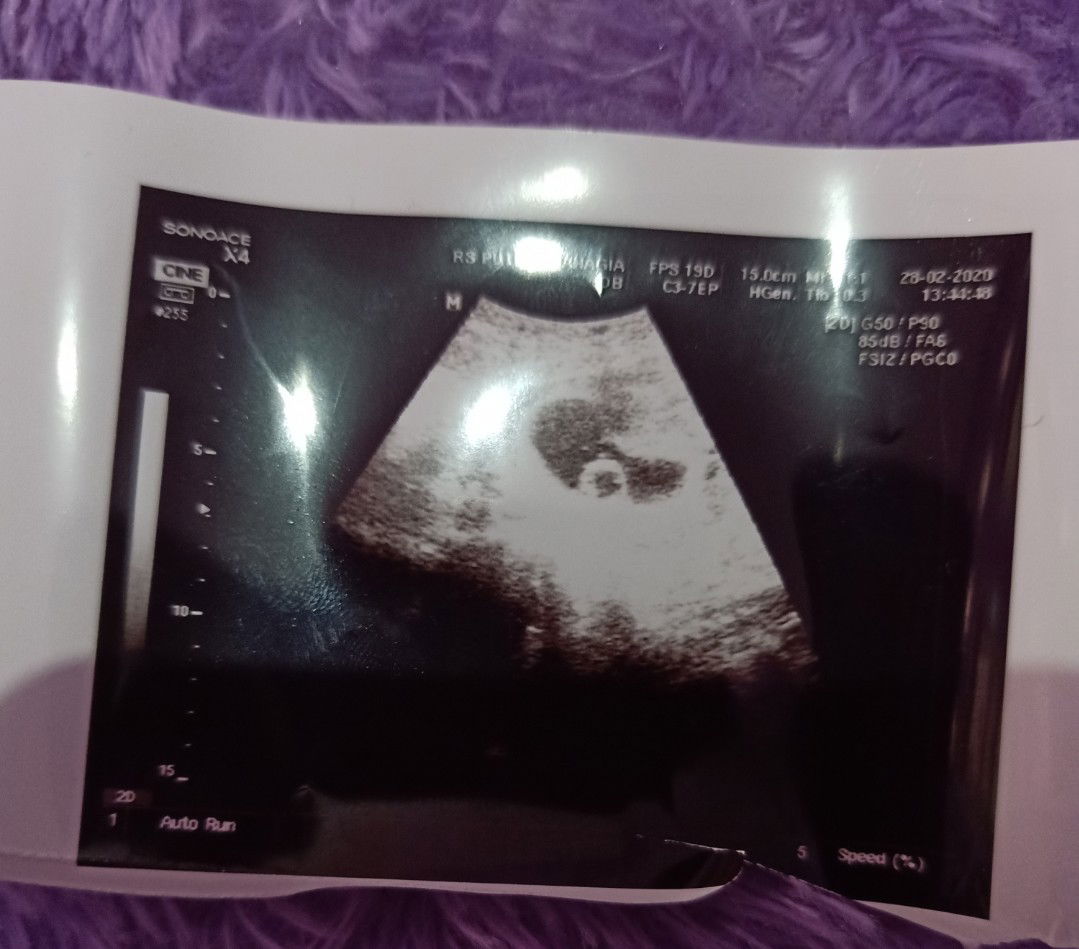

yolk sack

Assalamualaikum bunda Menurut HPHT sy hamil 8W... Dua mnggu yg lalu pas uk 5w5d msh trlihat kantung lalu sy usg lg pas uk 8W tp blm trlihat janin hnya kantung dan yolk sack (kuning telur)... Sblmnya sy BO diusia 8W... Sy tkt BO lg bun ? Apa ada bunda dsini yg prnh ngalamin ada yolk sac lalu kmudian ada janin ? Sy berusaha berfikir positif mgkn stlh yolk sack akan ada janin aamiin... ?